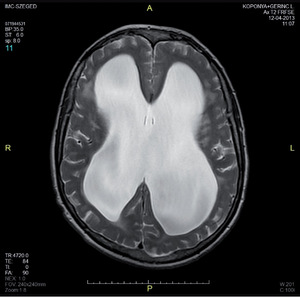

3.6.1. Hydrocephalus (59–63. ábra)

- Koponya-CT: kamrák mérete– frontalis kamraszarv/belső koponya átmérő,temporalis kamraszarvak nagysága,periventricularis liquorkilépés jele,külső liquorterek komprimáltsága.

- Koponya-MRI: kamrák mérete– a fentiek, valamint occlusiót okozó eltérés kimutatása,sagittalis képeken a III. kamra fenekének lenyomottsága,aqueductus stenosis kimutatása.